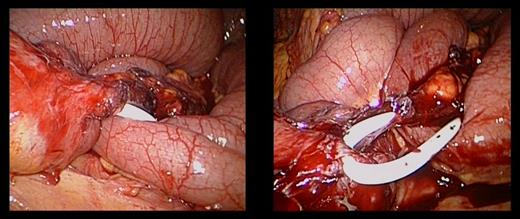

Two weeks later, she re-presented to the emergency department with a 24-hour history of severe central abdominal pain associated with vomiting and multiple episodes of loose stools. On examination, she was found to be hypotensive, tachycardic and peritonitic. The suspicion of an SBO was established by plain film radiograph appearances with multiple air fluid levels and distended bowel loops (Fig. 1). Computed tomography scan of the abdomen and pelvis showed the transitional zone to be in mid abdomen (Fig. 2). This was thought to be most likely secondary to adhesions. She proceeded on to have an emergency laparoscopy. Interestingly, the laparoscopy identified the transition point of the SBO to be an adhesion formed between the LAGB tube, the mid jejunum and the stomach forming a classic closed-loop obstruction (Fig. 3). The laparoscopic division of this adhesion was performed successfully. The rest of the small bowel was run along its entire length with no other transition point found. The adjustable gastric band was removed at the same time along with the associated port. Postoperatively, she had an uncomplicated recovery and was discharged on Day 4 post-admission without further sequelae.

The gastric band connection tube had formed a dense adhesion to the jejunum resulting in a tight obstructive band.